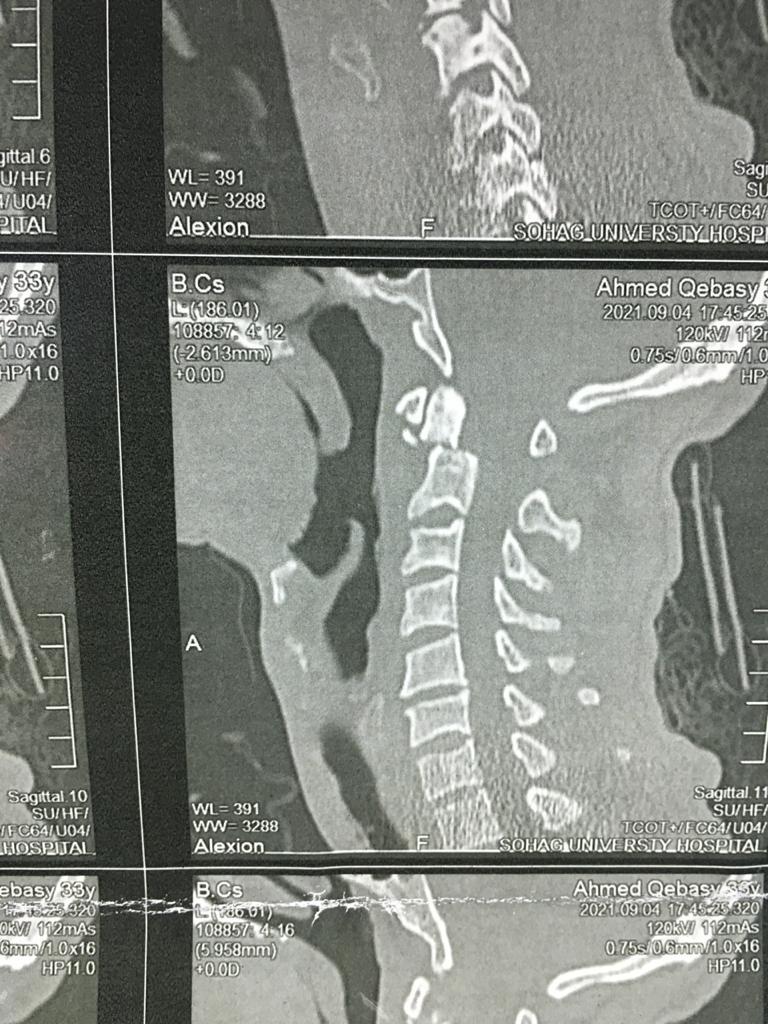

أكد الدكتور مصطفى عبد الخالق القائم بأعمال رئيس جامعة سوهاج أن فريق طبي متخصص من قسم جراحة العظام بالمستشفى الجامعي نجح في إجراء عملية جراحية لتثبيت كسر بالفقرة العنقية الثانية لشاب في العقد الثلاثين من عمره، وذلك بواسطة التدخل الجراحي من الأمام.

وقال "عبد الخالق" أن تلك الجراحة تعد من أكثر جراحات العمود الفقري خطورة نظرا لقربها من قاع المخ والحبل الشوكي وتحتاج إلى دقة ومهارة عالية في إجراؤها.

وأوضح الدكتور حمدي سعد مدير المستشفى الجامعي أنه بعد إجراء الفحوصات والإشاعات اللازمة للمريض تبين وجود كسر في الفقرة الثانية من العمود الفقري الرقبي، ويحتاج إلى جراحة عاجلة لتثبيت الفقرة العنقية، حيث كان هذا الكسر يشكل خطرًا كبيرًا على النخاع الشوكي وحياة المريض.

وذكر الدكتور عبدالرحمن الشيخ رئيس قسم جراحة العظام أنه بعد دراسة الحالة في ضوء نتائج الفحوصات الطبية، تم اتخاذ كافة التدابير التحضيرية للعملية، لافتًا الي ان الفريق الطبي الذي إجري العملية الجراحية للمريض كان تحت إشراف الدكتور أحمد صالح أستاذ جراحة العظام والعمود الفقري، حيث تم تثبيت الكسر بنجاح، وبدأ المريض الحركة بحرية تامة بمفرده بدون اي وسائل مساعدة.